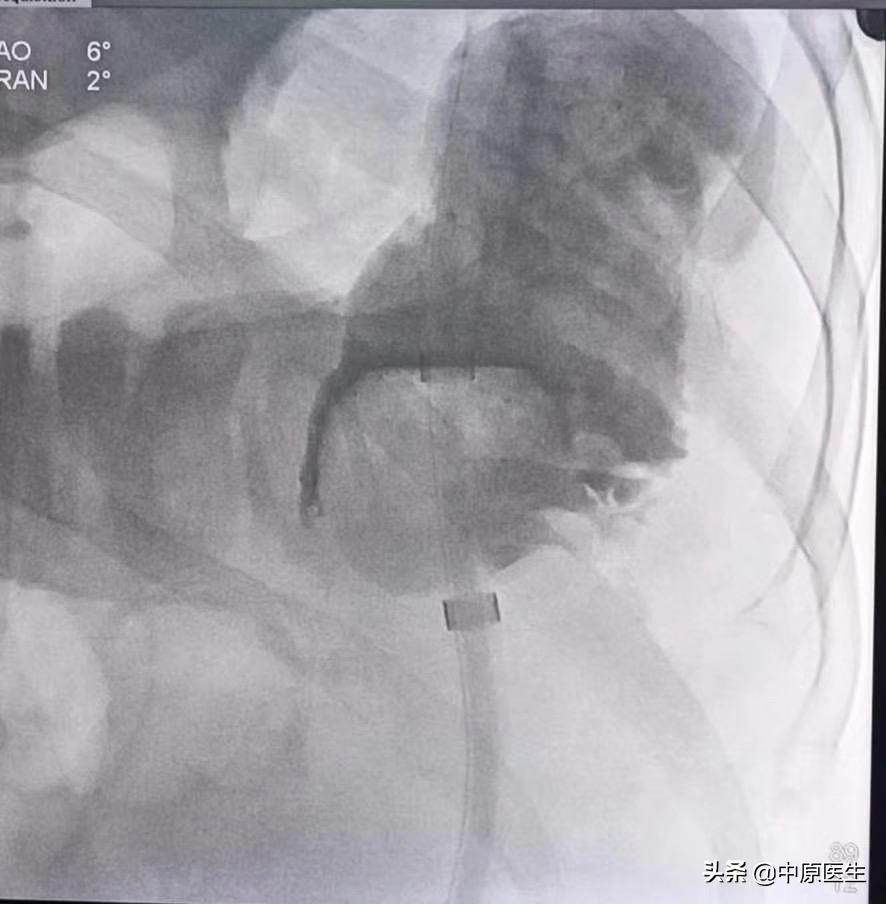

经过会诊,我们介入科刘建文教授团队决定通过介入方法帮助患者解决肿瘤引起梗阻的问题。25日,在导管室行局麻下消化道造影+降结肠球囊扩张+经肛型肠梗阻导管置入术。术中透视见腹部膨大,肠管明显扩张,膈肌上移。让患者取截石位仰卧,充分润滑、局麻后,我们送入超滑导丝、直径不到1mm的导管,反复尝试导丝通过闭塞处、送至横结肠脾曲处,但导管无法跟进,为了保留150cm的超滑导丝,将100cm的直径不到1mm导管分段剪断、依次撤出,再送入直径2mm的指引导管,再送入一根260cm的超滑加硬导丝,送至横结肠内,依次用10mm球囊、肠梗阻导管的扩张器反复扩张狭窄处,肠梗阻导管仍无法通过,再次同轴送入双导丝,应用16mm球囊多次扩张后,顺利把肠梗阻导管送至横结肠内,充盈导管头端球囊,将肠梗阻导管头端固定于降结肠梗阻处上方;淤积的肠气和部分肠液、粪便排入引流袋内,病人腹胀减轻。术中反复交换各种导丝、导管,带出不少臭屁、臭粪便。整个手术间都是不可描述的气味、手术台不忍直视。

这是刘建文、李陆鹏医生在完成12台手术后,迎来的最后一台手术。体力、精力都消耗很大。连年轻体壮的李陆鹏(大鹏)累的都受不住了,这台手术,刘建文医生吃射线透视时间102:49分。